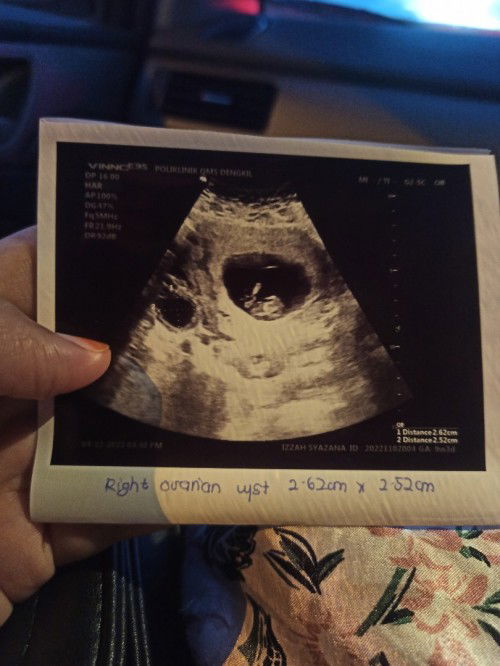

9 weeks scan ada cycs size 2 cm

Hi mommies , ada tak siapa2 yang ada pengalaman macam saya ? Scan tiba2 nampak ada cycs .. Boleh saya tahu apa langkah yang mommies buat untuk kecutkan cycs tersebut ? And cycs tu akan hilang kan bila baby membesar ? Saya takut sebab ada yang cakap , kene bedah untuk buang , risiko baby and mom .. #firstbaby #firstmom